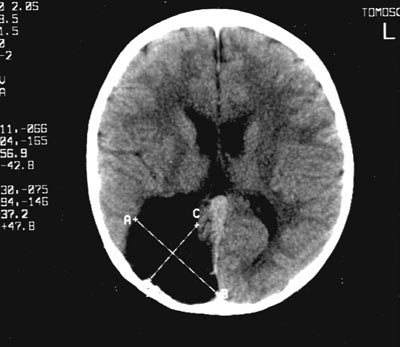

Пример V: одностороннее поражение затылочной доли мозга (Рис. 8-10). Пациентка 7 лет с последствиями черепно-мозговой травмы, полученной в результате автомобильной аварии. Жалобы на снижение зрения обоих глаз. Vis OD=0.1, OS=0.8, левосторонняя гомонимная гемианопсия с сужением правой половины поля зрения обоих глаз (OD до 6°°, OS до 20°°), на глазном дне билатерально определяются признаки атрофии зрительного нерва. С помощью МРТ визуализируется посттравматическая порэнцефалическая киста правой затылочной доли размером 60x44 мм, имеющая сообщение с задним отделом расширенного гомолатерального желудочка. Общая электроретинограмма OU нормальная. Топографическое картирование ЗВП: при стимуляции как OD, так и OS компонент P2 расширен, его латентность увеличена, доминирующий позитивный очаг определяется в контралатеральной по отношению к стимулируемому глазу теменно-затылочной области, в том числе над пораженной, правой затылочной долей. Источники ЗВП имеют различное расположение при стимуляции каждого глаза и локализуются при стимуляции OD в левой (контралатеральной) затылочной доле, а при стимуляции OS в затылочной и височной долях левого (ипсилатерального) полушария. Регистрация позитивного потенциала при стимуляции OS над пораженной затылочной долей объясняется ориентацией вектора дипольного источника, расположенного в левом полушарии, в сторону правой затылочной доли.

рис. 12. Поражение правой затылочной доли мозга. МРТ головного мозга